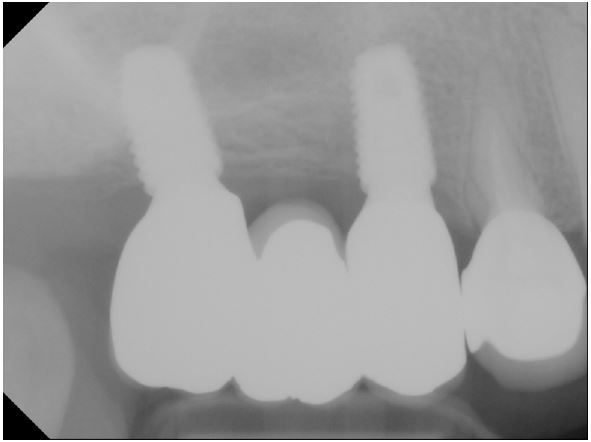

The final implant prosthesis was inserted in April 2022 in the prosthodontics department (Figs. 3 and 4). The patient underwent regular check-ups in the periodontology and prosthodontics departments, and no complications were reported. The patient also visited the otolaryngology department every 6 months to check for recurrence.